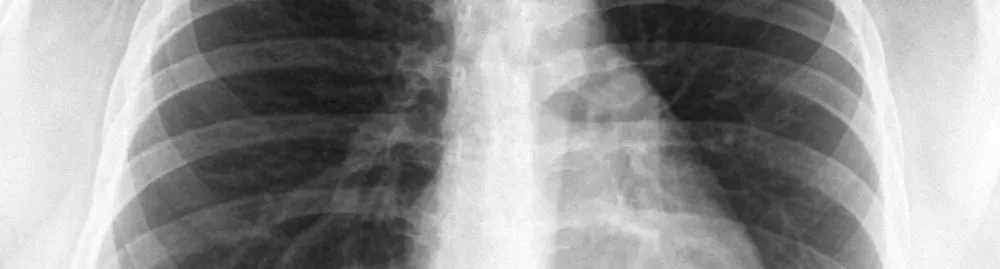

• O diagnóstico é confirmado por meio de exames de imagem, como radiografia de tórax e ultrassonografia, além da avaliação clínica

• Radiografia de tórax: é um dos primeiros exames a serem feitos, pois pode mostrar claramente a presença de líquido nos pulmões ou no espaço pleural